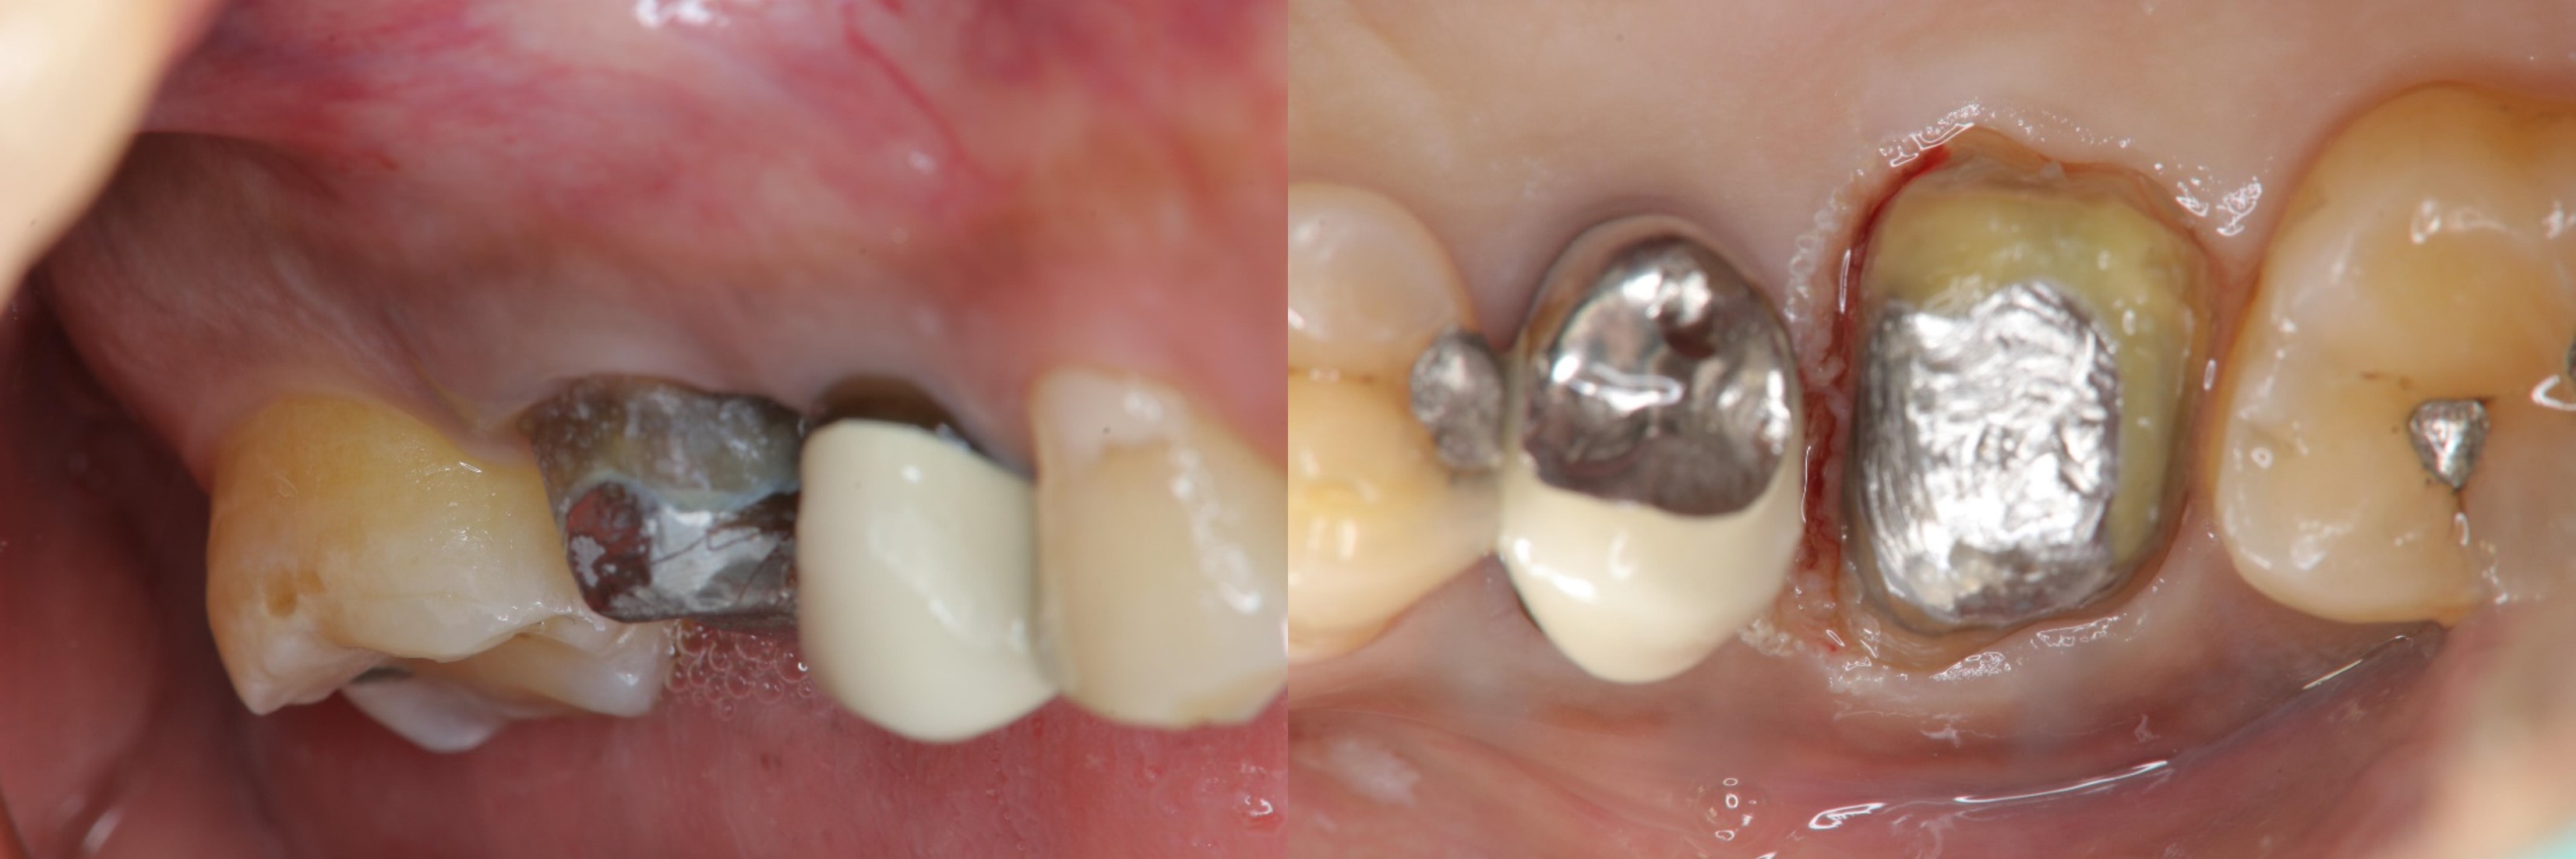

鑄造金屬釘柱

膺復前評估牙齦、牙齒狀態